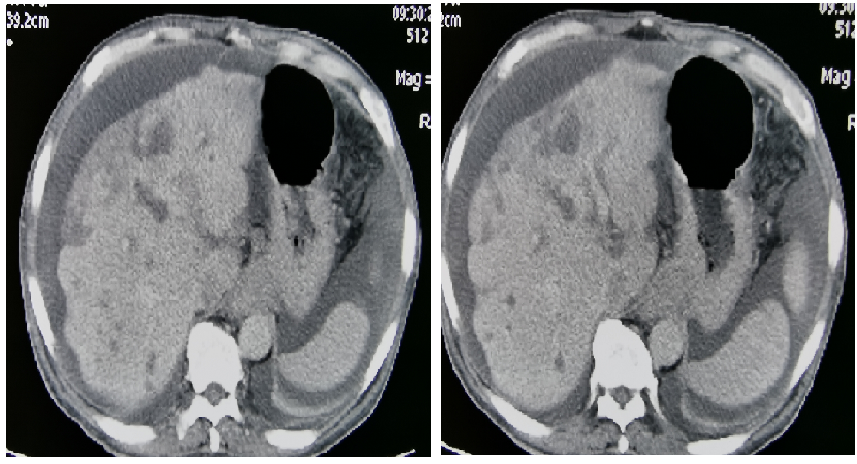

2018-11-05加入S1单药化疗,6次靶向+2周期S1化疗后,肿瘤标记物下降:CEA 947ug/L → 23.5ug/L血常规恢复正常。肿瘤明显缩小,范围变少。ECOG 1分

图3

病灶缩小,疗效评价:PR